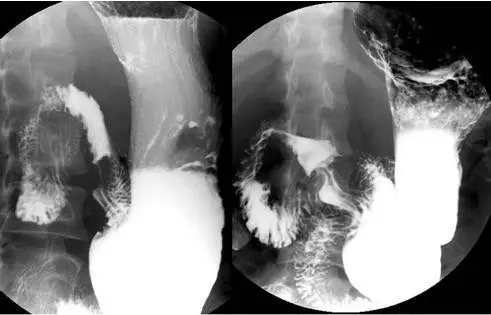

1、 胃肠钡餐检查

患者口服造影剂硫酸钡,在X光透视及拍片时,利用钡剂在胃肠道留下的影像来判断食管、胃和十二指肠内部的病变情况。此检查不能替代胃镜,不能行活检。更多的用于对胃下垂、胃动力异常、贲门失弛缓等方面。